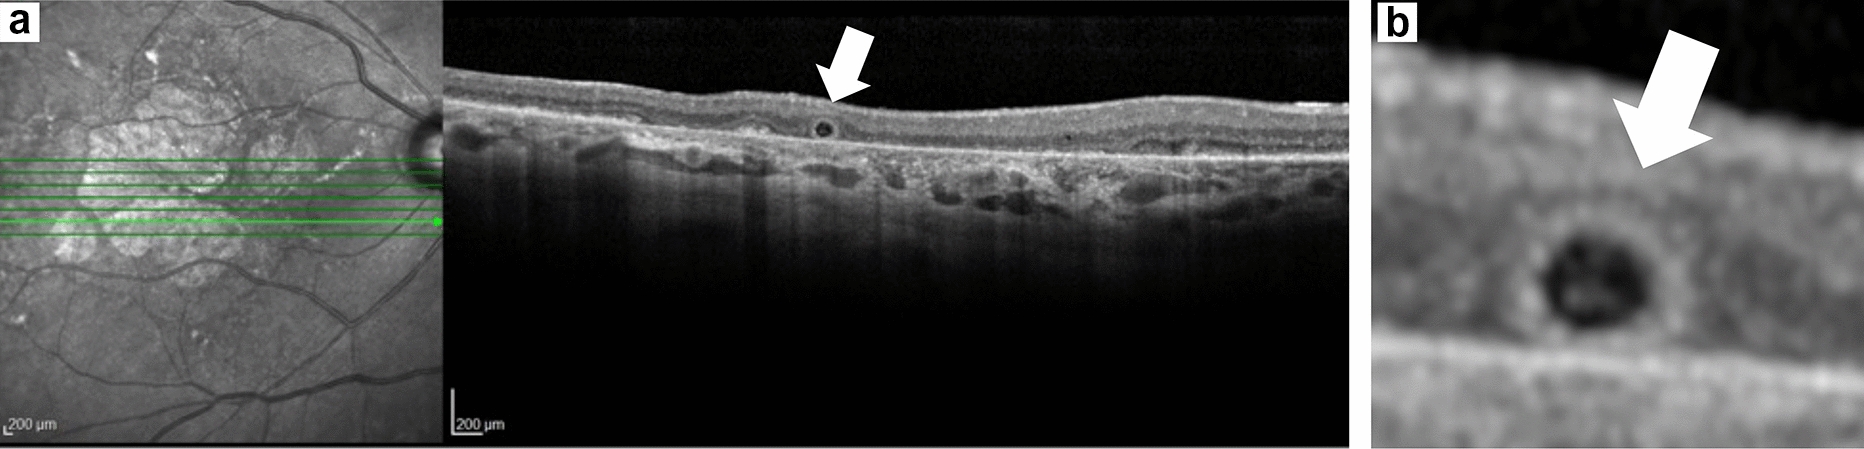

Fig. 1

ORT (white arrow) on cross sectional OCT (Spectralis, Heidelberg Engineering, Heidelberg, Germany) of a sham eye in the OAKS and DERBY trials (a) and magnified view of the region with ORT (b). Round hyporeflective core completely surrounded by a hyperreflective border and located in the region of GA. Note the choroidal hypertransmission and complete loss of the photoreceptor and RPE layers, consistent with advanced subfoveal GA. GA geographic atrophy, OCT optical coherence tomography, ORT outer retinal tubulation, RPE retinal pigment epithelium

This retrospective, longitudinal analysis included eyes randomized to the sham observed group from the 24-month phase 3 OAKS (NCT03525613) and DERBY (NCT03525600) trials [13]. For inclusion in this analysis, baseline OCT utilizing the Spectralis (Heidelberg Engineering, Heidelberg, Germany) and at least one post-baseline GA area measurement via fundus autofluorescence (FAF) were required. Two independent graders (KH, BS) evaluated all included eye OCT images at baseline, month 12, and month 24 for the presence or absence (dichotomic factor) of a fully formed ORT (Fig. 1a, b), with any discrepancies arbitrated by a third reader (SS). OCTs were evaluated by reviewing each of the 49 horizontal raster scans per eye for the presence of a fully formed ORT, which was defined as a hyperreflective circular border completely surrounding a hyporeflective core and located in the outer nuclear layer. Independent reading center (Digital Angiography Reading Center, Great Neck, NY, USA) evaluation using OCT and FAF classified GA location as either subfoveal or nonsubfoveal based on the distance from the atrophy border to the center point of the fovea, with a distance of ≥ 1 µm defining nonsubfoveal GA. The change in GA area was based on baseline ORT status and was assessed as the square root of the total GA area (millimeters) as measured by FAF over 24 months. GA measurements were graded by the same reading center and utilized independent manual measurements of GA features; mean area was determined by two masked readers, while the median area was determined by three readers. Within-group t tests were performed to compare changes from baseline in square root of total GA area at months 12 and 24 between eyes with ORT versus eyes without ORT at baseline.